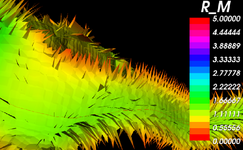

NEW: BRAINSDemonWarp (Hans Johnson)

Plastimatch non-rigid registration (Greg Sharp)